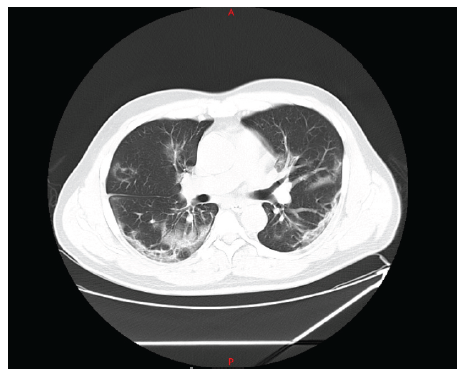

The patient is a 44-year-old male, residing in Colombia, who was admitted to the emergency room on November 24, 2020. His illness started on November 15, 2020, due to fever of 38-39 degrees Celsius, dry cough, anosmia. He presented positive PCR test for SARS CoV2 on November 17. During the first 4 days, he manifested intermittent episodes of dyspnea and chest pain, so he decided to go to the emergency room, where the diagnosis of atypical viral pneumonia was confirmed. Initially, oxygen saturation and inflammatory markers were normal, and it was suggested to continue treatment at home. On November 24, he was readmitted due to worsening symptoms presenting desaturation and dyspnea on exertion. His chest CT scan on admission showed a mixed pattern with ground-glass infiltrates and bilateral diffuse alveolar consolidation (figure 1).

Due to moderate hypoxemia, computed axial tomography results, and increased inflammatory markers, in-hospital management in the intensive care unit was initially advised to keep the patient under continuous monitoring of vital signs. Initial management with steroids (Dexamethasone 6mg IV, every 24 hours) and oxygen therapy with nasal cannula at 28%, but with the need to increase Fio2, due to increased dyspnea.